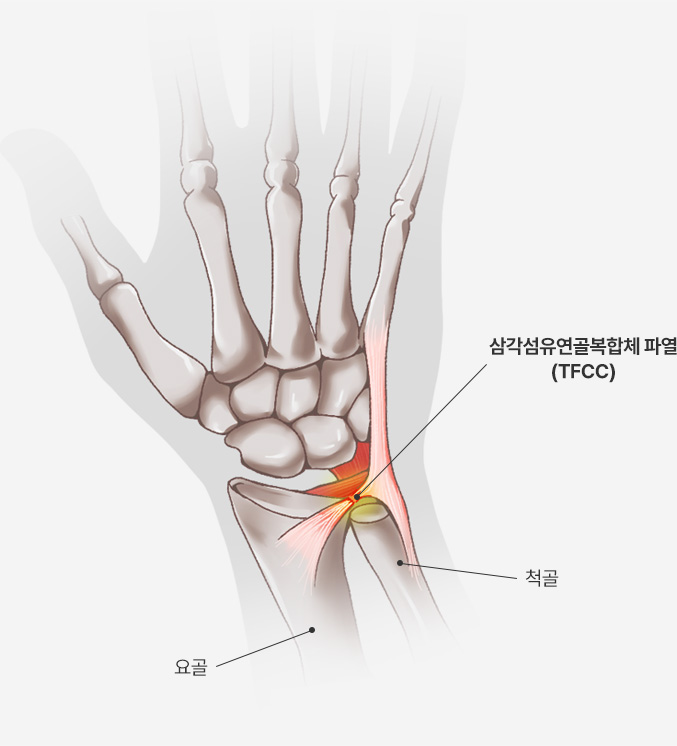

손목의 새끼손가락 쪽에 위치한 삼각형 모양의 연골 및 인대 복합체이며, 손목 관절의 안정성 유지 및 충격 흡수의 역할을 합니다.

또한 요골과 척골 사이의 움직임을 조절하고, 손목의 회전 운동을 보조합니다.

삼각섬유연골복합체 파열이 있을 경우 MRI 에서 다음과 같이 뼈 부착부에서의 파열(빨간 원)과

관절액이 원위요척관절로 새어 나온 이차적인 변화(노란 원)이 관찰됩니다.